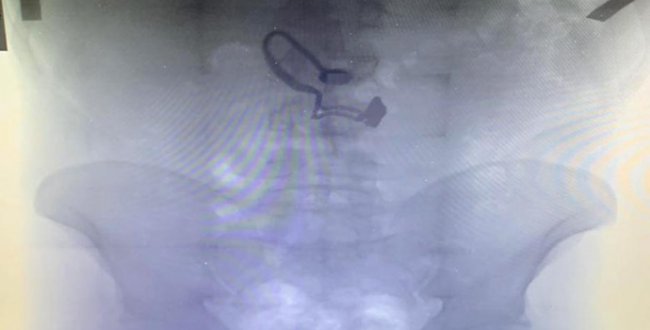

У столиці перехожі спіймали грабіжника: крадене знайшли у шлунку (ФОТО)

Столичні жителі затримали чоловіка, який пограбував перехожу і проковтнув ланцюжок, зірваний з її шиї. Про це повідомляє прес-служба поліції Києва, – передає Українська правда. Подія сталася у Голосіївському […]